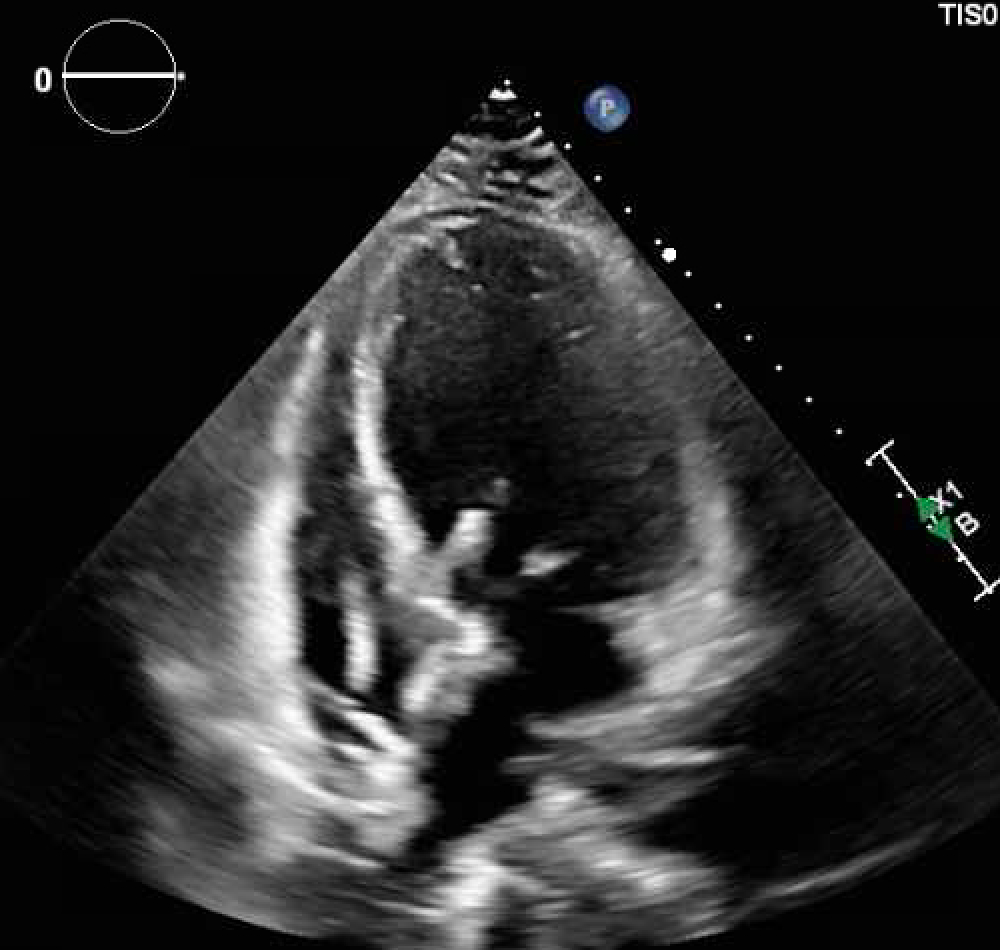

A 49-year-old female with past medical history of asthma initially presented to an outside hospital for palpitations, chest pain, and hypertension. Transthoracic echo (TTE) showed preserved left ventricle ejection fraction (LVEF) while cardiac MRI showed a LVEF of 43% with dilated left ventricle and diffuse global hypokinesis consistent with a dilated cardiomyopathy. She underwent a coronary angiogram demonstrating nonobstructive CAD. She was then discharged with readmission a month later at our hospital for chest tightness, palpitations, vomiting, weakness, and dizziness. Repeat TTE showed a drop in LVEF to 10-15%. She progressed to cardiogenic shock requiring BiPAP and inotrope initiation, with progressive shock and hypotension ultimately requiring Impella 5.5 and venoartrial ECMO. Abdominal imaging was notable for 4.7 x 4.2 cm right adrenal nodule and further workup with serum and urine metanephrines confirmed pheochromocytoma. While supported, the patient underwent right adrenalectomy with subsequent wean of mechanical circulatory support and biventricular recovery on TTE.